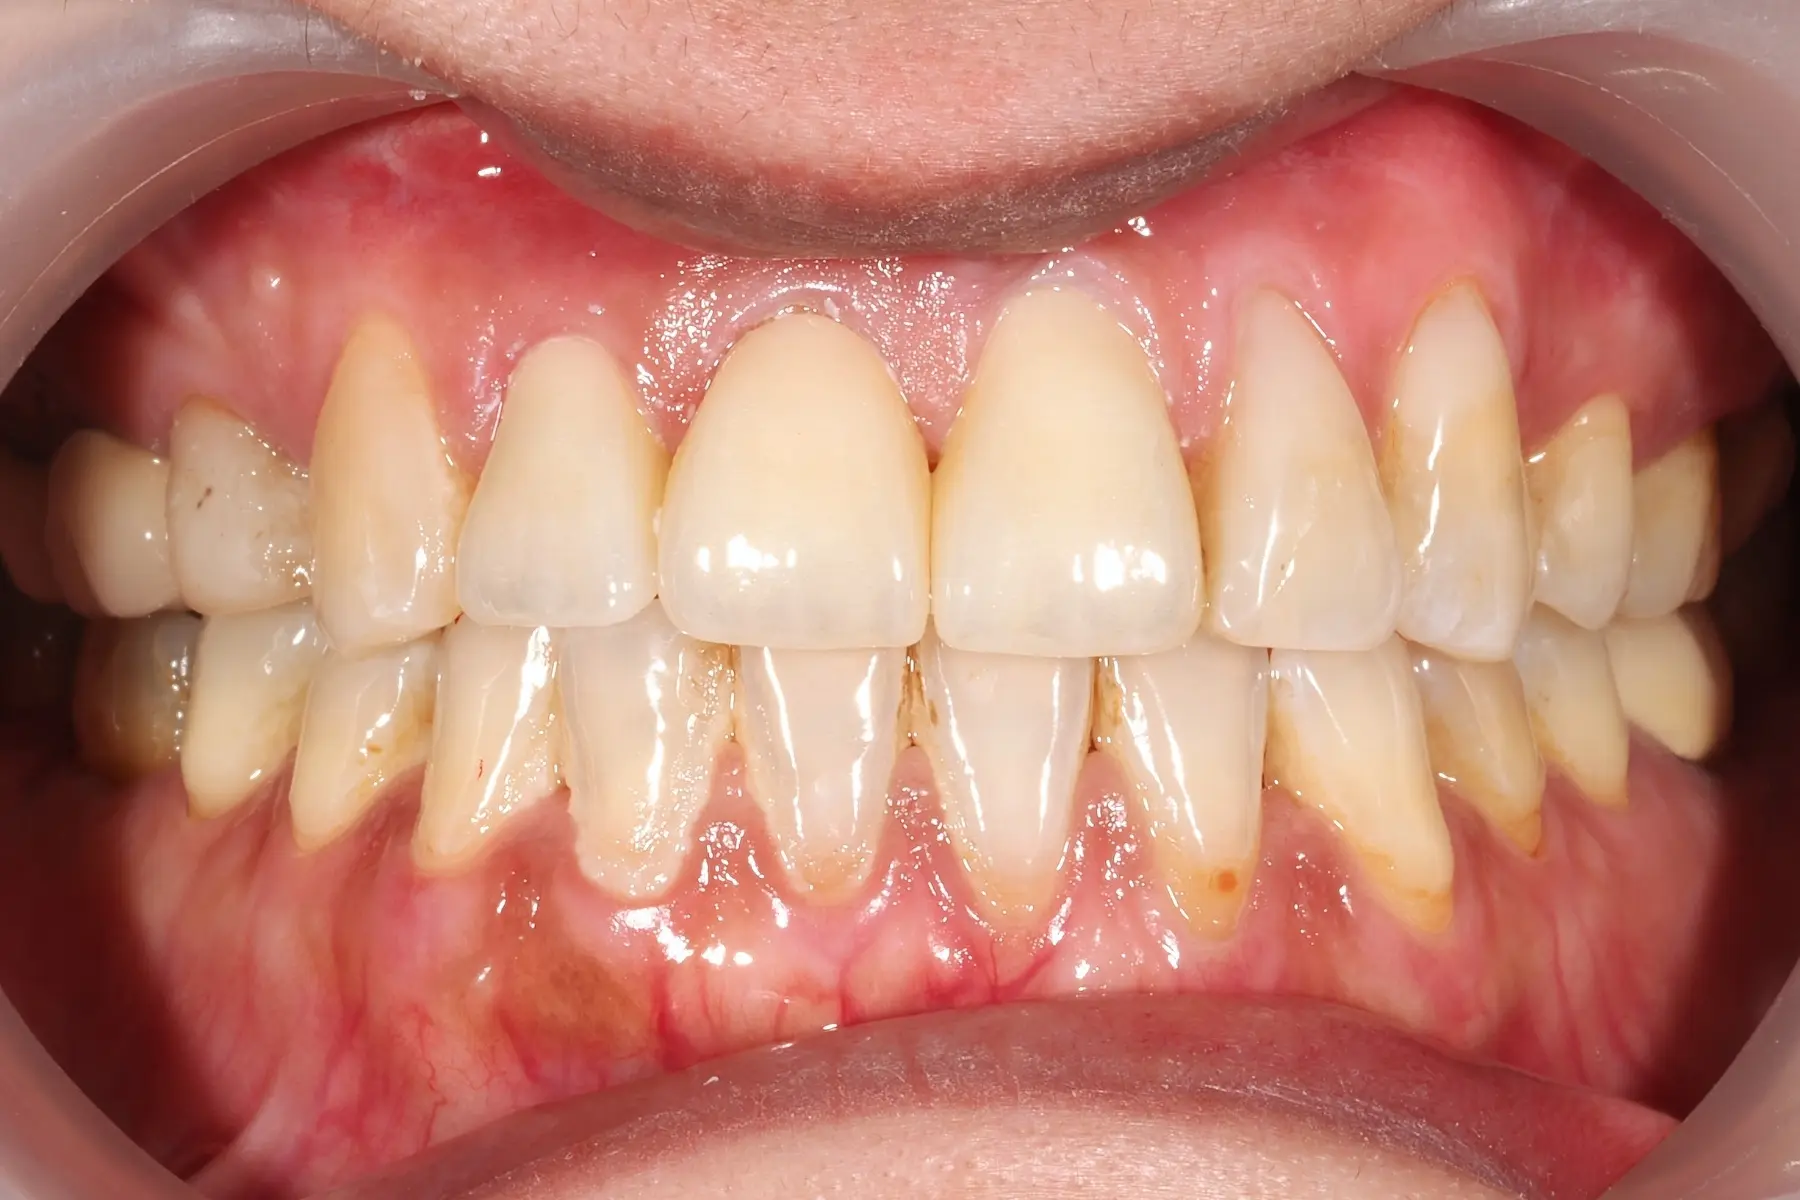

牙齦紅腫出血、牙縫容易塞食物

• 術前 42

術後 40

牙周治療

主治醫師

• 鍾國耀

治療時間

三次療程

主訴

右上前牙牙齦反覆腫脹化膿